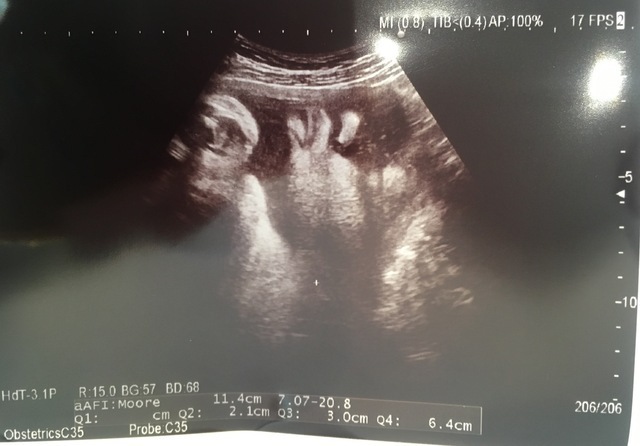

30週5日(30w5d・男の子)|ハルくんmama さん(24歳)

エコー写真撮影時のエピソード:

妊娠26週目に先天性の私の病気が見つかり、出産まで入退院を繰り返しました。妊娠中ということでしっかりとした治療が出来ず、経過観察しつつ、少しでも状態が悪くなれば緊急帝王切開で出産になります、とNICUの説明も受けて、常にハラハラドキドキでした。

そんな入院中の唯一の楽しみが週に1度エコーで赤ちゃんを見ることでした。このエコーは全てのエコーの中で1番お顔がハッキリみえた上に性別が確定したときのものです。